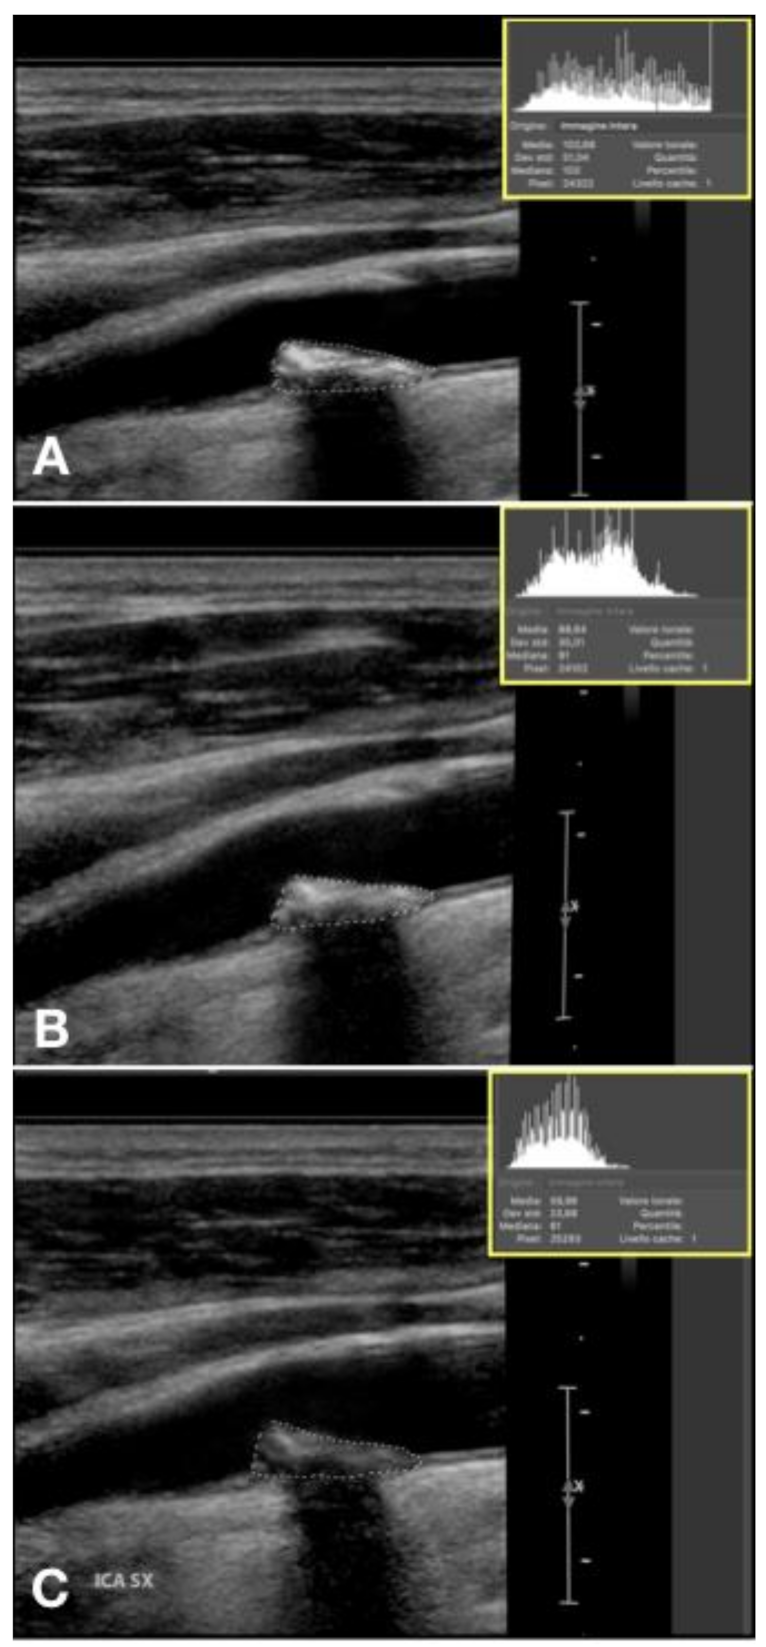

Figure 8.

Proportion of subjects with and without a GSM reduction of 15 points at 12 months.

Figure 9.

Plaque showing echogenicity decrease in 12 months treatment with vitamin K2. (A) start, GSM 103, (B) 6 months, GSM 91, (C) 12 months, GSM 61.